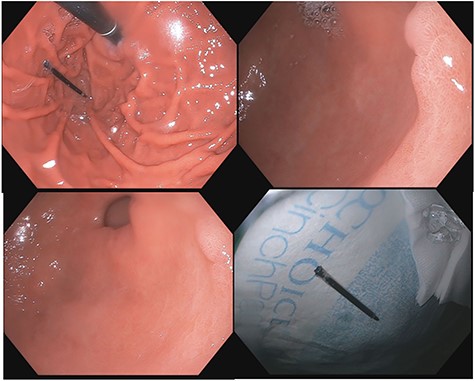

A 43-year-old incarcerated woman with borderline personality disorder and a long history of swallowing various foreign objects in periods of stress presented to the emergency department after swallowing a cup of bleach. Her surgical history was significant for multiple celiotomies for retrievals of purposefully ingested foreign bodies. During evaluation, she also admitted to swallowing an ink pen 3 weeks prior to swallowing the bleach for which she did not seek medical evaluation. She reported no food intolerance or changes in bowel function secondary to swallowing these objects. She presented with mild abdominal pain and cramping, and her vital signs and laboratory investigations were all within normal limits. Her abdominal exam was notable for mild tenderness to palpation diffusely. Computed tomography (CT) of the abdomen (Fig. 4) showed a linear foreign body in the distal gastric antrum penetrating the inferior wall and extending into the adjacent peritoneal fat. No free air or free fluid was appreciated. Initial esophagogastroduodenoscopy (EGD) was significant for mild erythema and edema to the esophageal and duodenal mucosa as a result of the caustic ingestion, and the pen was found to be deeply perforating the stomach antral wall with no associated ulcer or edema (Fig. 1). The depth at which the foreign body was lodged was uncertain, so there was concern for organ involvement outside of the gastric wall. Repeat EGD was done to assess for manifestations of esophageal, gastric or duodenal injuries from her caustic ingestion, and it revealed normal gastric mucosa (Fig. 2). A joint case was planned with the gastroenterology service for endoscopic foreign body retrieval, possible laparoscopic retrieval and gastric repair and possible open retrieval and gastric repair. The patient was taken to the operating room for the third EGD, which revealed spontaneous migration of the foreign body from the perforation site into the lumen of the gastric body (Fig. 3a). Additionally, there was spontaneous closure of the site of previous perforation (Fig. 3b and c). The ink pen was easily removed transorally using an endoscopic snare, and no further surgical intervention was required. After the procedure, the patient reported complete resolution of her abdominal pain and was able to tolerate a regular diet without problems.

(a–d) Subsequent EGD 1 week later; (a) foreign body in the fundus of the stomach; (b and c) irregularity in the antrum corresponding to site of previous perforation; (d) ink pen after transoral endoscopic removal.

Side-by-side comparison of foreign body perforating through stomach (right) and sealed site of perforation after endoscopic removal (left).